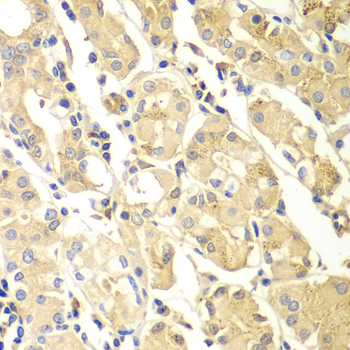

• A7394: image 2

Immunohistochemistry of paraffin-embedded human gastric using PDCD2L antibody at dilution of 1:100 (x400 lens).